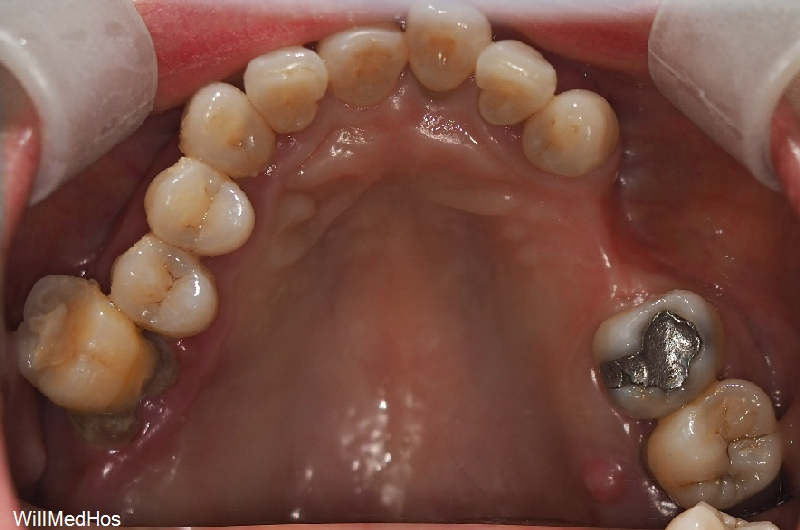

오늘 말씀 드릴 환자분은 10년 가까이 치과에 오시지

않으시다가 내원 해주신 환자분 입니다.

환자분의 초진 구강 사진부터 보도록 할께요.

이미 자연 발치와 치과에서 발치 진단을 받으시고 발치 후 10년 가까이 치아들을

방치 해놓으신 상태라 위의 치아들이 정출되어 내려오기도 하고 관리가 아예 안되신 상태 이셨습니다.